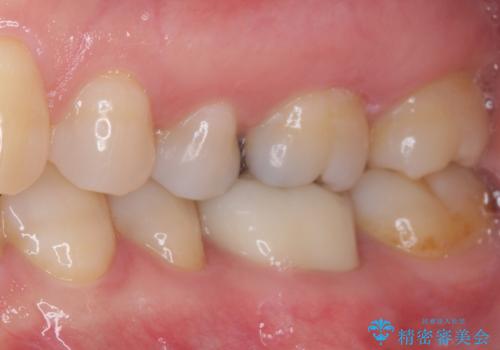

- 上下の奥歯に違和感を感じ、近医にて虫歯を指摘されたとのことで来院された患者様です。

診査したところ、下顎の奥歯は膿の出口ができており、上顎の奥歯は噛んだときに痛みを感じている状態でした。

まずは根管治療を行い、症状が落ち着いたことを確認して、オールセラミッククラウンにて補綴治療を行うこととしました。